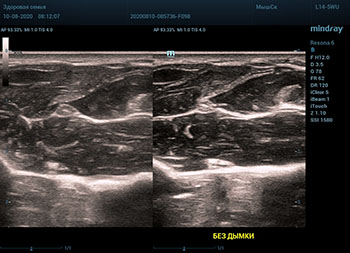

В приборах серии Resona, компании Mindray, появилась новая функция постобработки изображения. Имя ей Dehaze. В переводе на наш родной язык – удаление дымки или рассеивание тумана. Инструмент позволяет корректировать интенсивность тумана или дымки. При этом сохраняется общий контраст и детализация картинки. Dehaze также позволяет проявлять детали снимка в гиперэхогенных зонах и снимать артефакты при чрезмерном усилении.

Готовый снимок или видео петля в формате DICOM несет в себе полное нативное изображение. Прибор позволяет, подобно легендарному фотошопу, удалить лишний «туман». Гиперэхогенный диффузный «засвет» изображения, из-за повышенного общего усиления, часто вредит обследованию. Однако без него некоторые вещи не видны. Показать гипоэхогенные участки и скрыть эхогенную дымку и позволяет Dehaze.

Всё что требуется от доктора – нажать кнопку или повернуть ручку. Мгновенная оптимизация. Мгновенно чистое изображение.